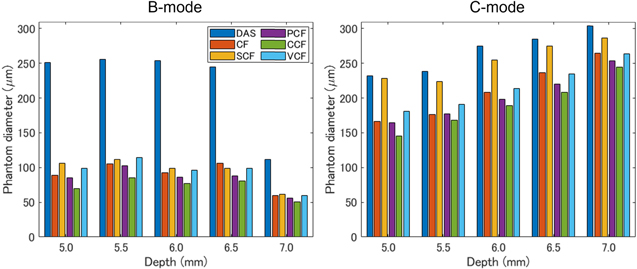

As one of the results of the phantom study, the images generated when the phantom was 5.0 mm away from the annular array are shown in Fig. 4. Figure 5 also shows the visualized phantom diameters in each MAP image of the phantom study visualized at all depths. Furthermore, Table I shows the sharpening ratio by applying each coherence factor method to the DAS beamformed signals.

Standard image High-resolution imageFig. 5. (Color online) The measured phantom diameters in the B-mode and C-mode MAP images of the 100 μm tube placed at 5.0, 5.5, 6.0, 6.5 and 7.0 mm from the transducer.

In the B-mode image, the phantom image visualized with the DAS method was thicker than the original diameter, especially at depths of 5.0–6.5 mm, which was more than twice as thick as the original diameter of 100 μm. In contrast, all types of coherence factors showed a high effect of sharpening. However, in the case of the CCF method, the diameter of the phantom was thinner than 100 μm at all depths. At a depth of 7.0 mm, the diameter of the visualized phantom was thinner than the original diameter when several types of coherence factors were applied.

In the C-mode image, the phantom image visualized with the DAS method was thicker than the original diameter, which was more than twice as thick as the original diameter of 100 μm, similar to the B-mode. On the other hand, the effects of sharpening by all types of coherence factors were confirmed at all depths. The CCF method showed the highest sharpening effect as well as B-mode. However, the effect of sharpening by the SCF method was small than the other coherence factors. The width of the phantom visualized by C-mode tended to be thicker in the deeper position.

5.1. Phantom study

In the phantom study, the improvement effect for image quality by applying the five coherence factors was evaluated by calculating the sharpening ratio of the phantom diameter at different imaging depths. In the B-mode and C-mode MAP images of the phantom study, the results suggested that the five coherence factors had a high effect of sharpening. However, in the B-mode MAP images at a depth of 7.0 mm, the phantom diameter visualized by applying the DAS method suddenly decreased and was confirmed to be around 100 μm. This may be attributed to the decrease in SNR of the PA signal in the deep region due to laser attenuation. In particular, the depth of 7.0 mm is deeper than the acoustic focal length of 6 mm, which is affected by both the influence of the laser attenuation and the decrease in the receiver sensitivity outside of the ultrasound focal length. Therefore, it is suggested that the phantom was not properly reconstructed due to the rapid degradation of signal reception sensitivity caused by these factors.

In the C-mode MAP images of the phantom study, the visualized phantom diameters were found to be larger than the true diameter at all depths and they were increased according to the depth. The reason for the lineally overestimation may be the linear degradation of the resolution and the measurement error due to the mechanical scanning. In the former case, the DAS method made the focal length variable, resulting in a linear change in the phantom diameter with a small  at deeper depths. In the latter case, the original phantom diameter is approximately three pixels in size, which means that the phantom is visualized at a depth of 5.0 mm with a spread of two or three pixels at both edges of the phantom. This indicates that the phantom was overestimated due to the measurement error caused by the mechanical scanning.

In the phantom study, the diameter of the visualized microtube in B-mode and C-mode was sharpened by applying any coherence factor, and the effect was significant especially in B-mode. Among the coherence factor methods applied in this study, the CCF method had the largest sharpening effect in B-mode, but the phantom diameter was visualized thinner than the original diameter in B-mode. In addition, the SCF method had a small effect of sharpening for C-mode images.